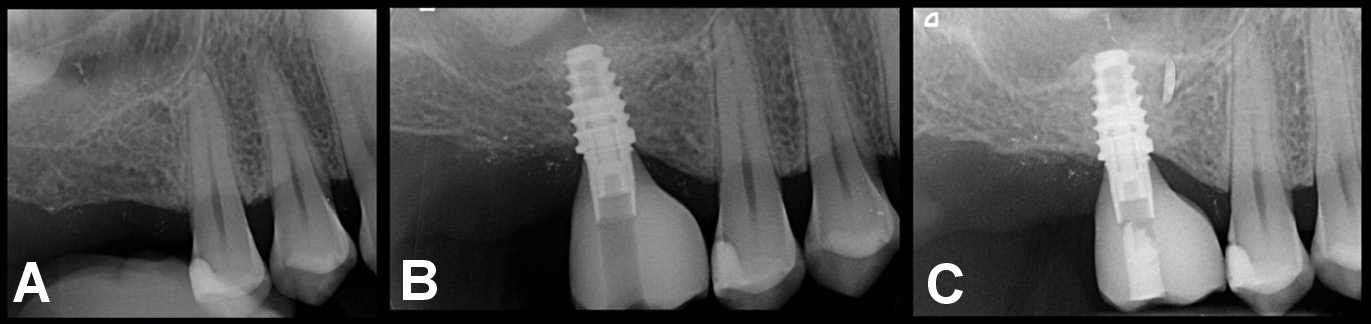

The analysis included 84 patients (44 men (52.4%) and 40 women (47.6%); mean age: 52.49 ±11.23 years) who underwent implant therapy between December 2015 and December 2018. Patients with severely atrophied, partially edentulous ridges (Classes III and IV according to Cawood and Howell19), with ≥8 mm of residual bone height and a thickness of ≥6 mm who received at least 1 short implant (≤7.5 mm) supporting a single crown were included in the study (Figure 2). Smokers, patients with periodontal disease (treated or untreated) and individuals with systemic conditions not considered absolute contraindications to implant surgery were included. Intraoral radiographs, CBCT scans, diagnostic wax patterns, and surgical templates were used for presurgical evaluation. At the end of the follow-up period (mean (M): 4.2 ±0.8 years), a total of 132 short implants were evaluated.

Short implants with a platform switch and a laser-microgrooved coronal design (Tapered Short; BioHorizons, Birmingham, USA) were used in all patients (Figure 3). The implants varied in diameter (4.6 mm and 5.8 mm) and length (6.0 mm and 7.5 mm), depending on the bone dimensions at each site.

Regarding CBL, the mean values recorded after 5 years of follow-up were 0.38 ±0.7 mm at the mesial aspect and 0.39 ±0.6 mm at the distal aspect (Figure 4). Mean MBL values were higher in smokers (0.64 ±0.6 mm), periodontally compromised patients (0.66 ±0.4 mm) and females (0.61 ±0.7 mm). These differences were statistically significant.